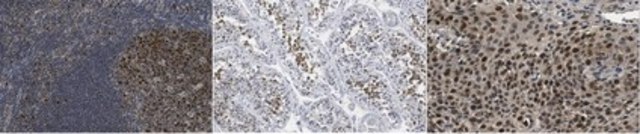

Immunohistochemistry Analysis: A 1:250 dilution from a representative lot detected MCM5 in human testis and human cervical cancer tissues.

Evaluated by Immunohistochemistry in human tonsil tissue.

Immunohistochemistry Analysis: A 1:250 dilution of this antibody detected MCM5 in human tonsil tissue.